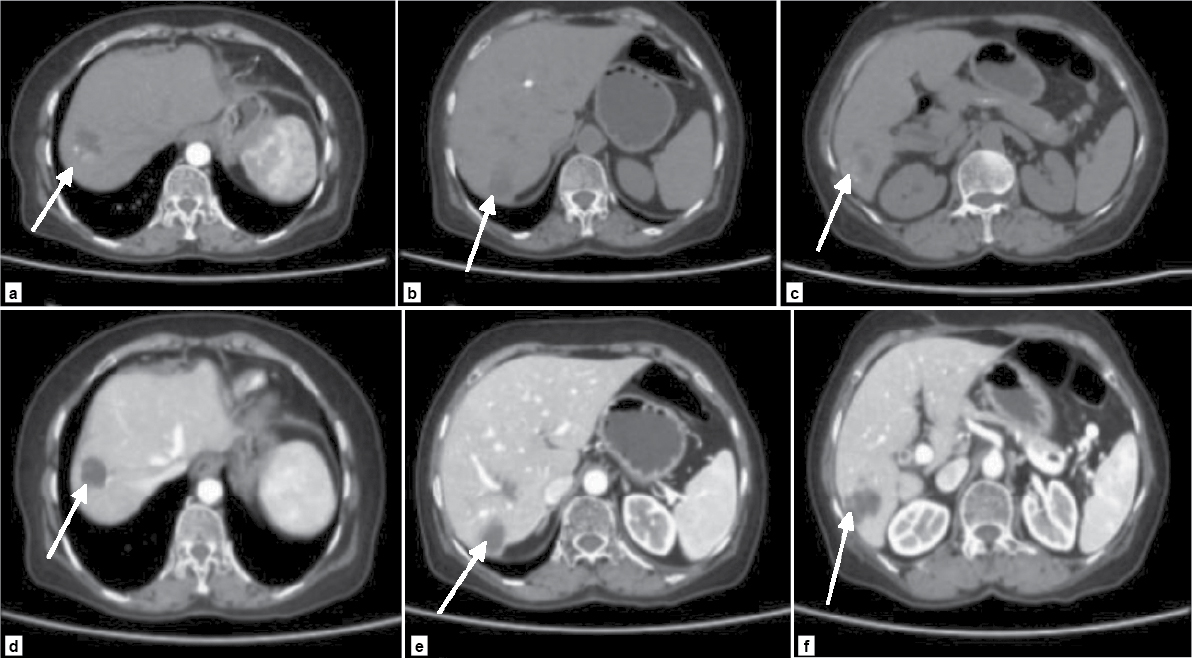

A differential diagnosis of resolving liver abscess or pancreatic pathology was considered. Further evaluation with 640-slice computed tomography (CT) abdomen showed multiple peripherally enhancing lobulated lesions with internal calcifications involving segments 6, 7 and 8 of right hepatic lobe (Fig. 1 a-f). Few lesions appeared tubular/serpiginous and were located in the subcapsular region (Fig. 2). Imaging was in favor of liver trematodes as the cause of liver abscess. A liver biopsy was done and histopathology of the tissue showed necrotic liver parenchyma with degenerated parts of parasite, likely a trematode (Fig. 3 a and b). Gram stain, acid-fast stain, fungal stain, Xpert Mycobacterium tuberculosis and tissue culture and sensitivity of the sample were negative. Since liver function tests were normal, endoscopic retrograde cholangiopancreatography (ERCP) was deferred and a decision to start medical management was taken. Patient was started on oral nitazoxanide 500 mg 3 times a day for 3 weeks. During follow-up, the patient was found to have no further fever spikes and her right upper quadrant pain had significantly reduced.

Figure 1 (a-f). CT images of liver showing multiple peripherally enhancing lobulated lesions in the right lobe of liver. Few lesions in the subcapsular region can be seen.